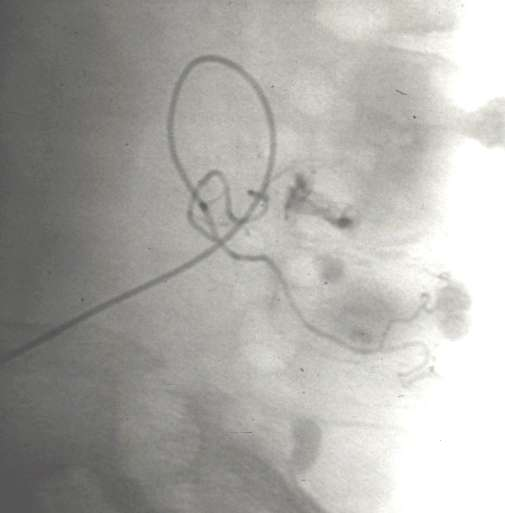

下消化道出血,微弹簧栓子直小动脉栓塞

乙状结肠出血:超越边缘动脉栓塞